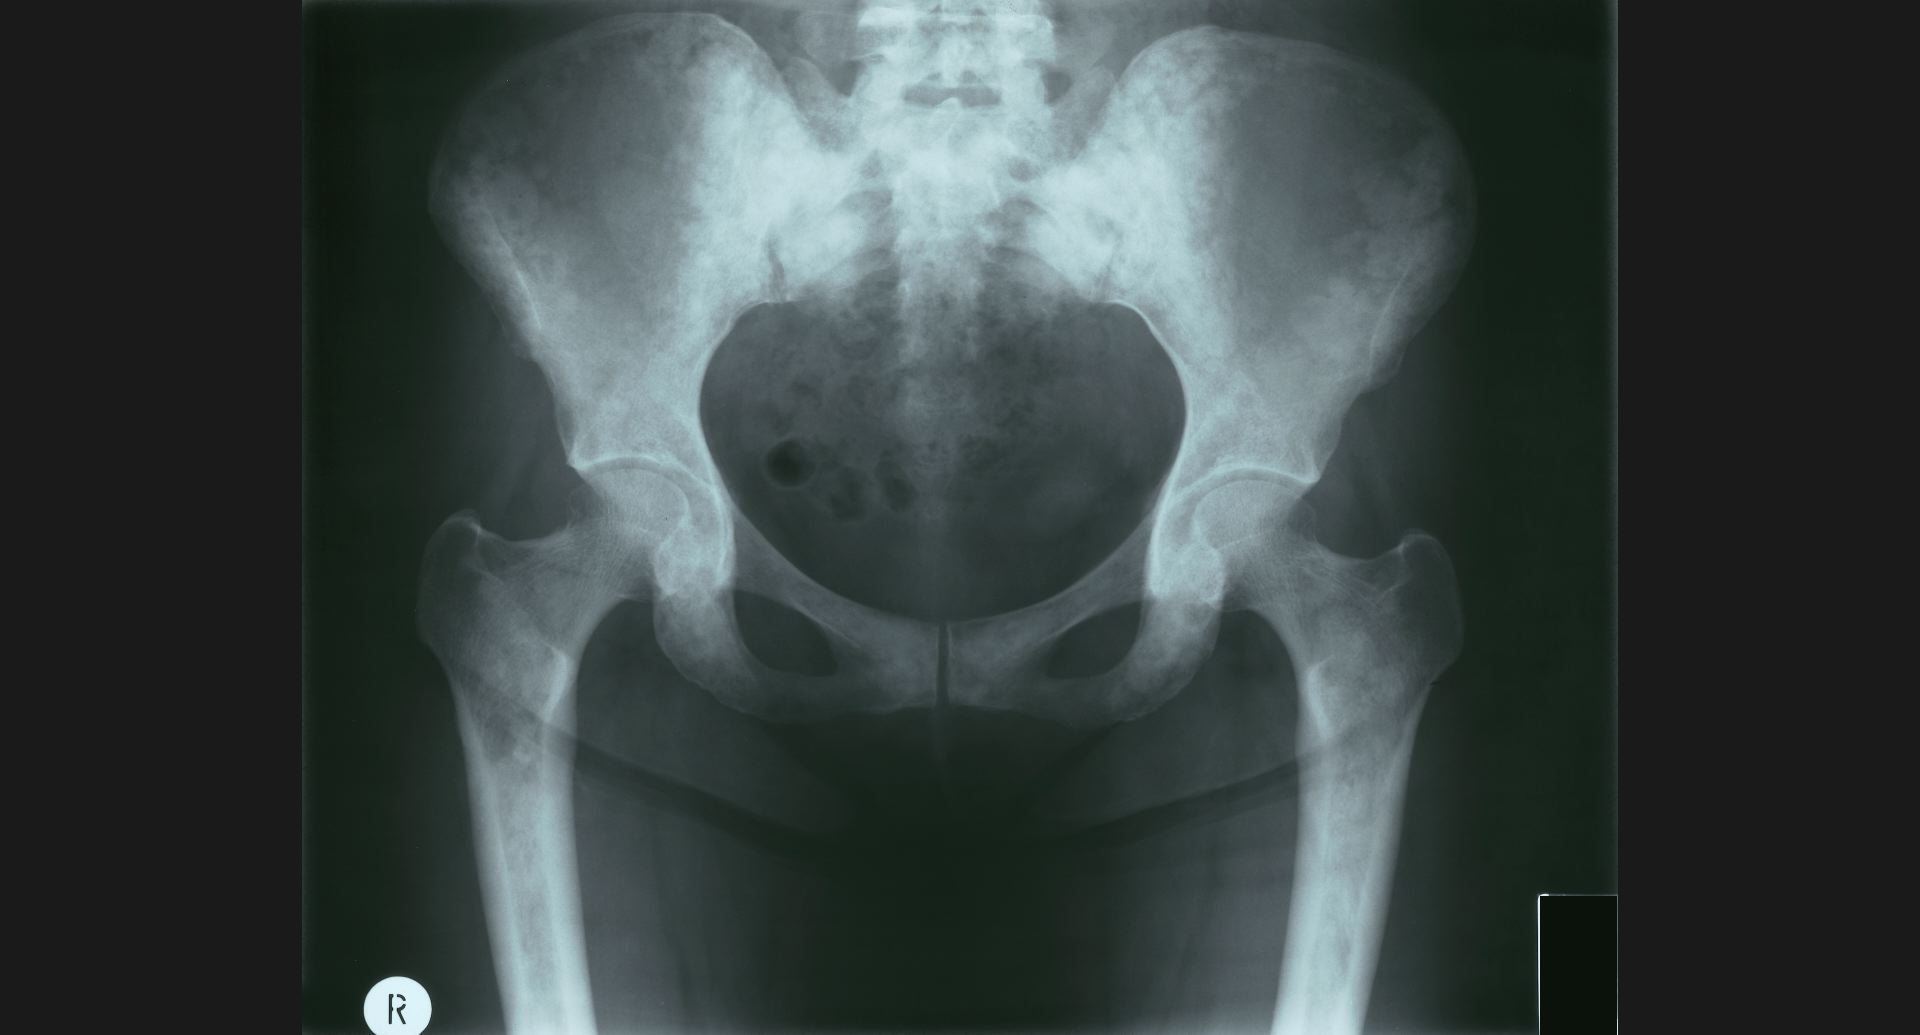

fig.16(93KB) :Osteoblastic metastases (骨盤)